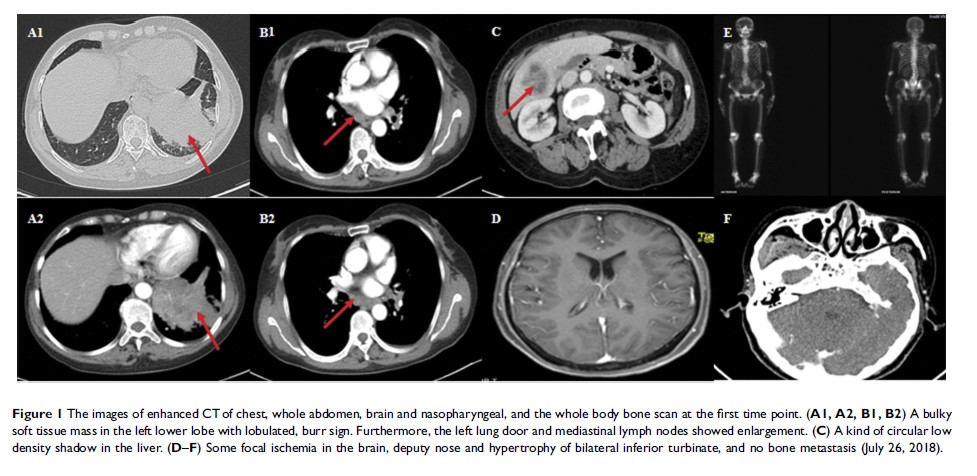

原发性肺淋巴上皮瘤样癌对纳武单抗的不良反应:1 份病例报告